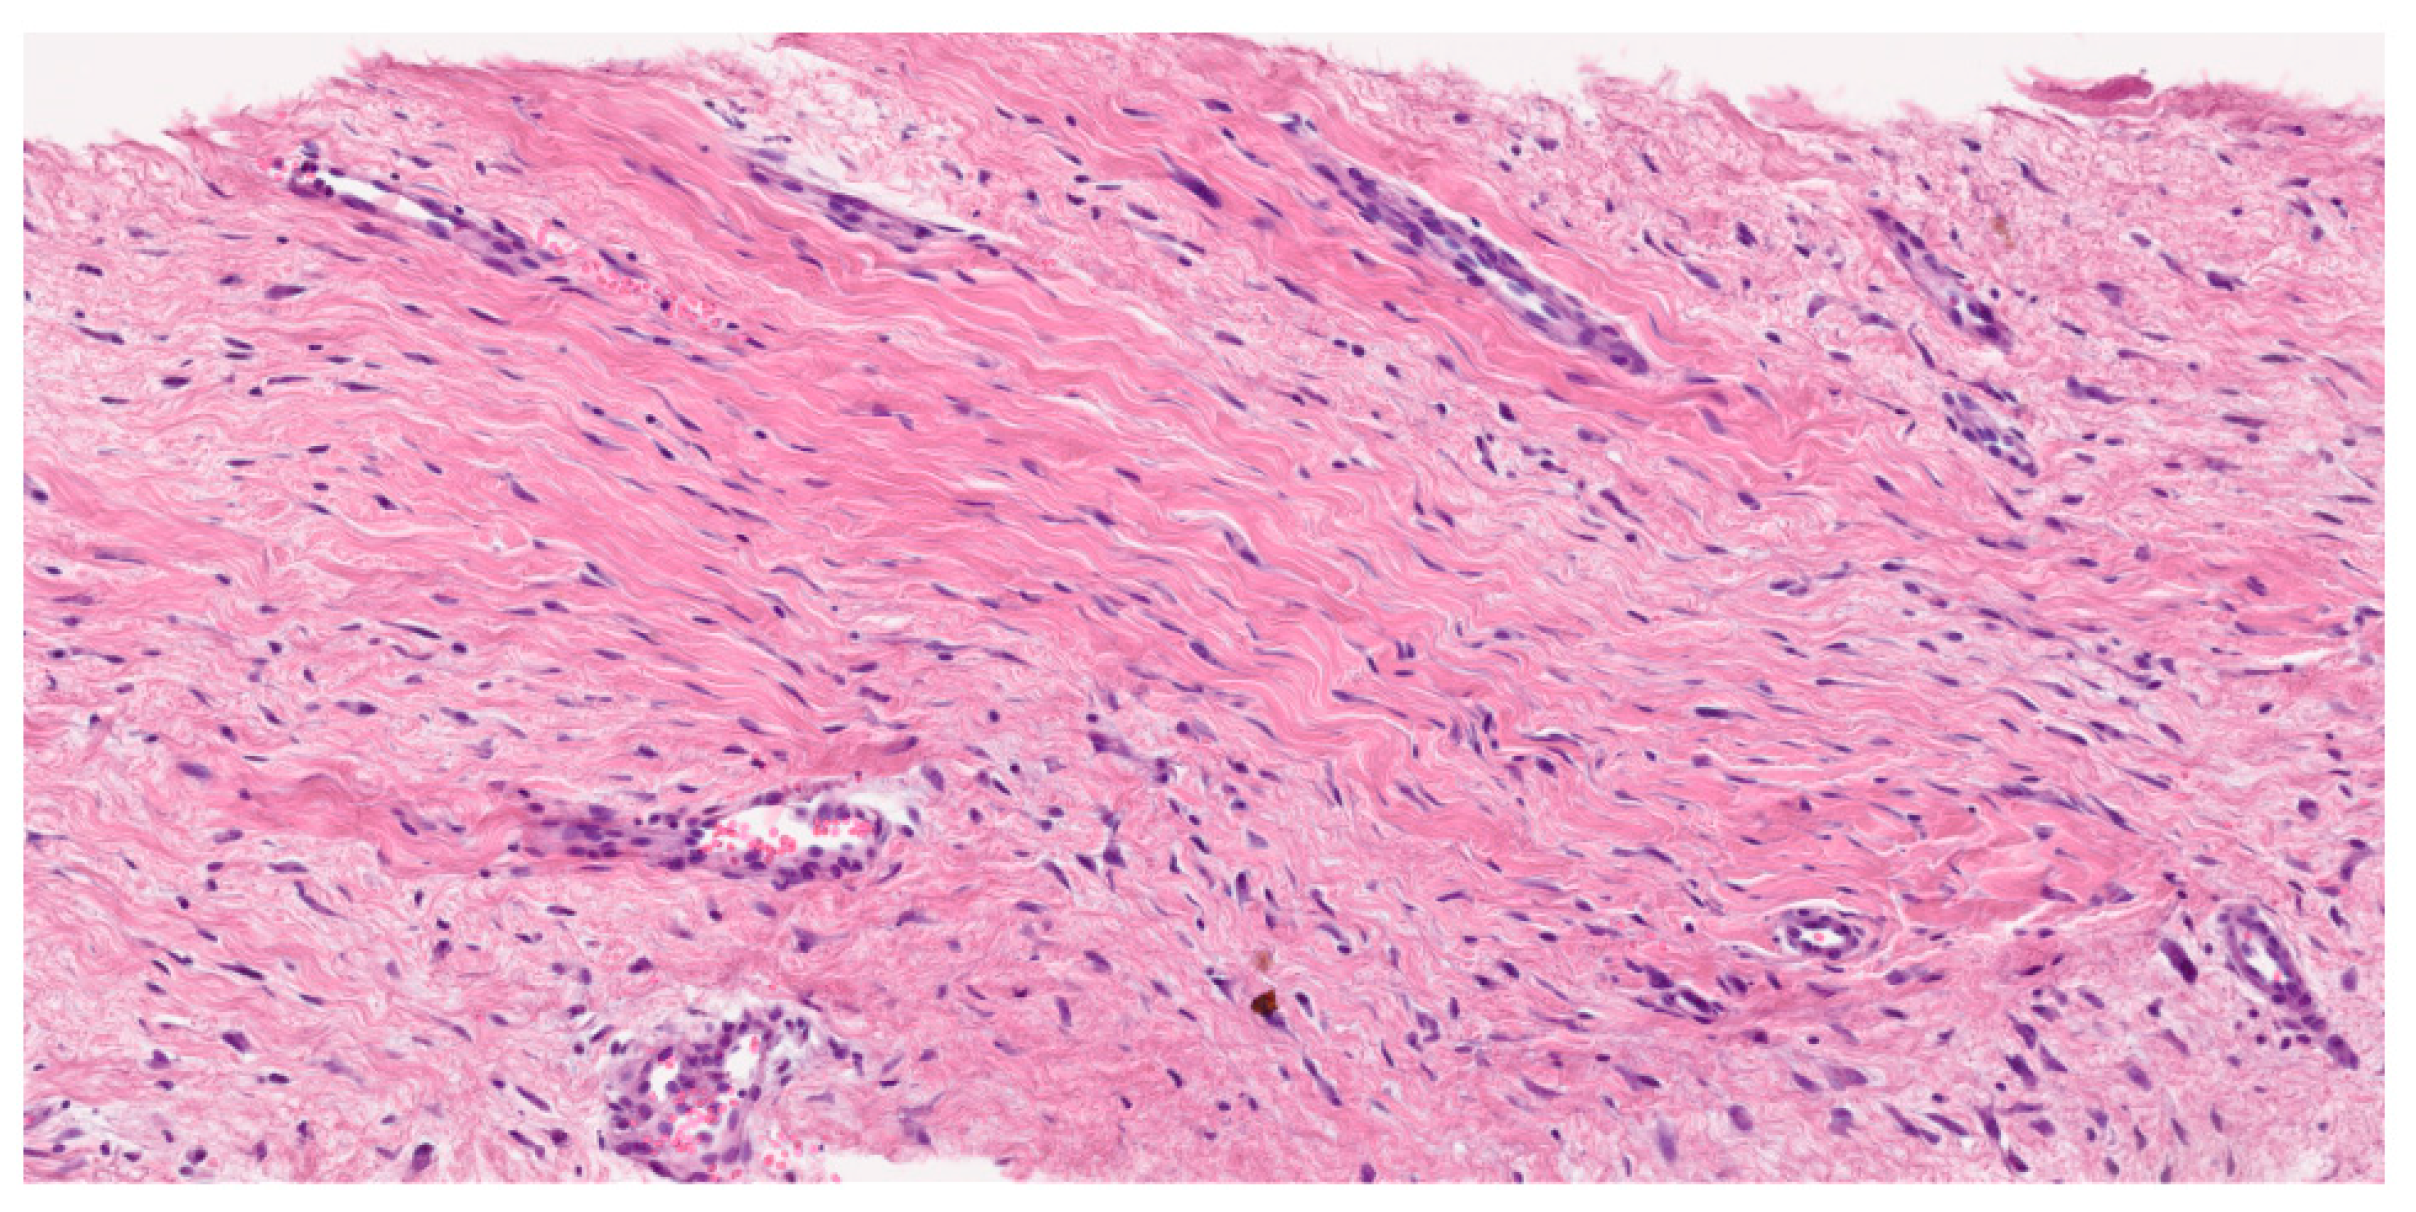

3.3. Histological Diagnosis

- Pathological diagnosis should be made by a sarcoma expert pathologist according to the most current WHO classification of soft tissue and bone tumors (IV, A).